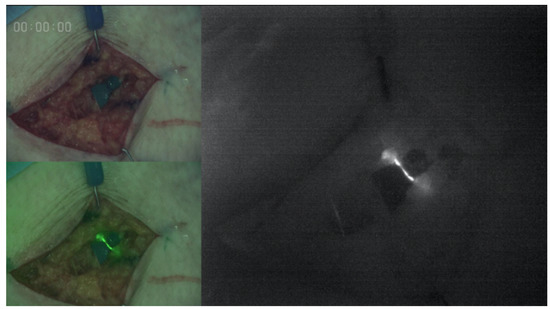

3.3. ICG Findings After Anastomosis